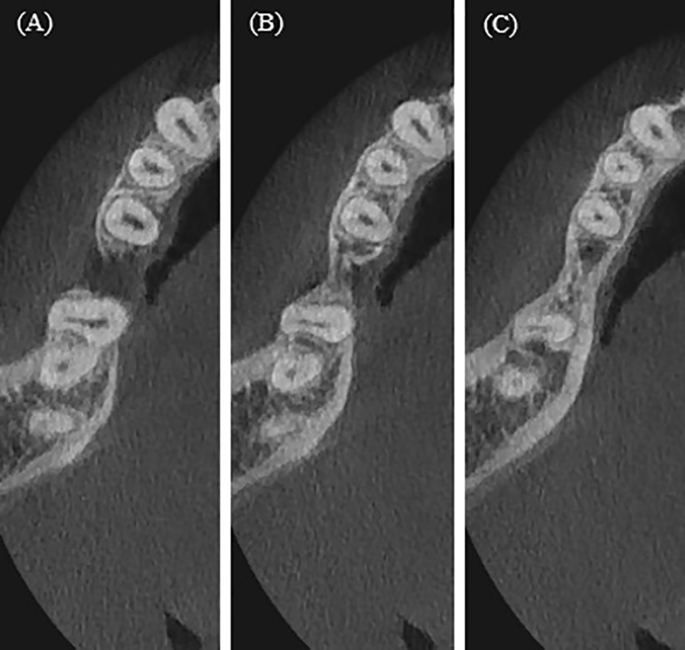

An analysis of the cross-sectional root canal shape and the changes along its entire length, made it possible to establish constant canals that don’t change their shape and canals with a change shape. A change in the root canal shape was observed in the middle part, in the apical, as well as in both the middle and apical parts. This change in the root canal shape to oval or ribbon-like, especially in the middle or apical parts, makes it problematic to prepare this part of the root canal with a round instrument (Fig. 6).

Example of cross-sectional root canal shape change from coronal third in mandibular second molars. (A–C) A case of changing shape from ribbon-like in mesial root to round in the apical third and from oval to round in distal root. (D–F) A case of changing oval shape in mesial root coronal third to ribbon like in middle and apical thirds.